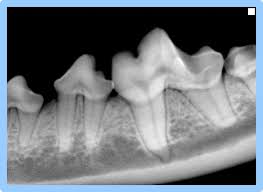

L’intervention la plus courante consiste en un détartrage des dents à l’aide d’un appareil à ultrasons du même type que celui utilisé chez votre dentiste.

Les détartrages sont réalisés dans le but de préserver les dents ou de freiner l’évolution de maladies dentaires (maladie parodontale par exemple).